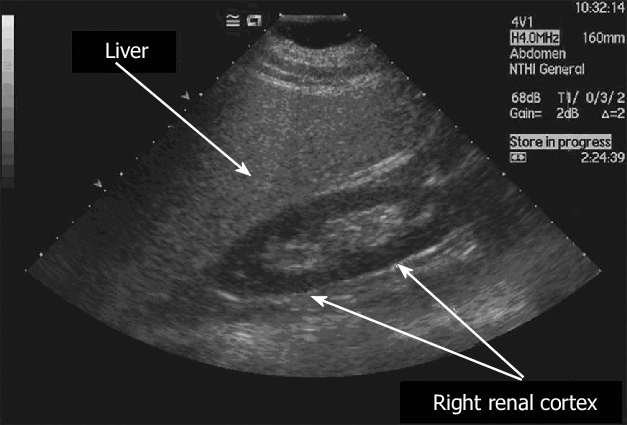

УЗИ печени позволяет выявить жировую инфильтрацию (стеатоз) — самое распространённое неинфекционное заболевание печени на сегодняшний день. Признаком стеатоза служит более высокая эхогенность или «яркость» печени в сравнении с эхогенностью почки. Понятие «эхогенность» предполагает плотность ткани органа, которая на мониторе УЗ-аппарата отображается серым цветом. В норме эхогенность печени совпадает с эхогенностью почки.

УЗИ способно выявить стеатоз печени, когда около 20–30 % печёночных клеток имеют включения в виде жировых капель.